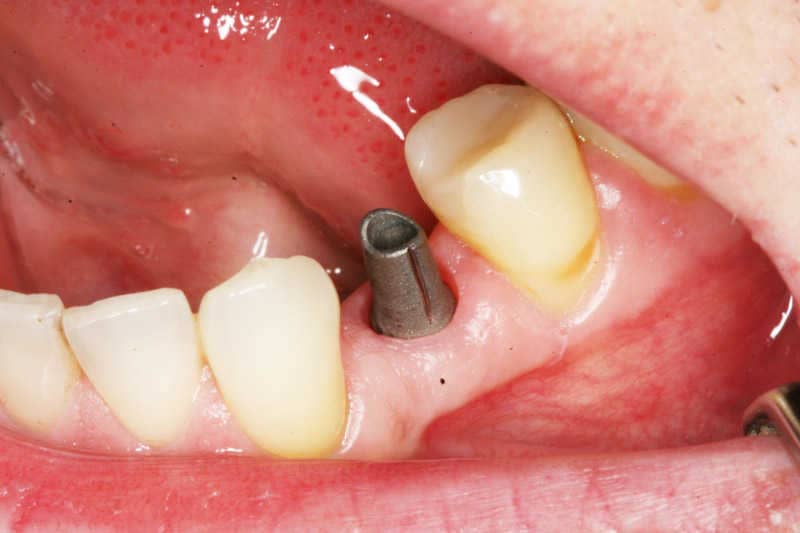

1

A foghiány helyére rögzített NobelReplace implantátum gyógyulócsavarral